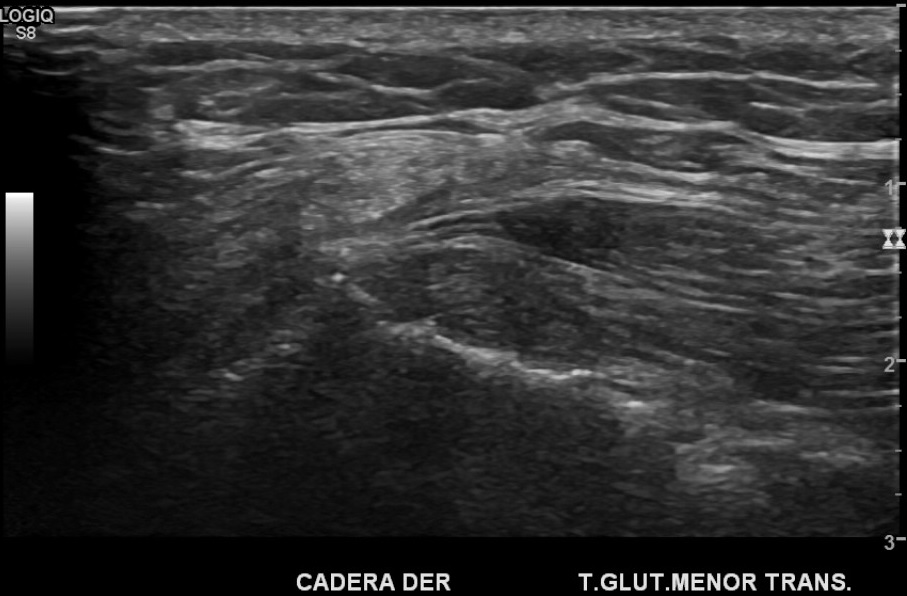

Hallazgos: En relación a la lesión palpable se observa engrosamiento nodular fusiforme del nervio cutáneo femoral lateral, hipoecogénico, sin flujo detectable al power doppler. Además, se observa heterogeneidad y engrosamiento del tendón glúteo menor, sugerente de neuroma y tendinosis del glúteo menor.